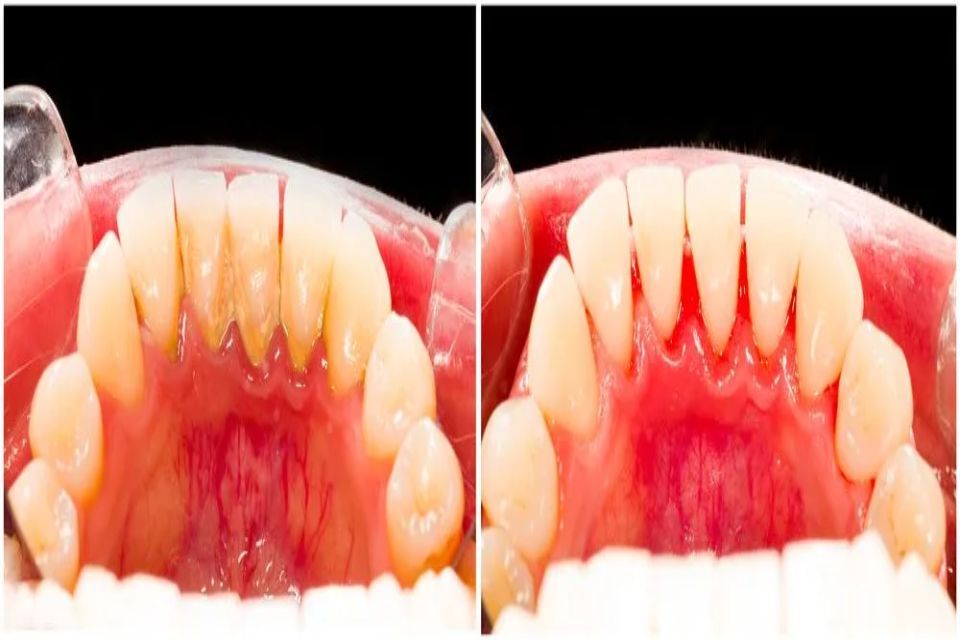

Lo studio offre le migliori soluzioni nel campo dell’odontoiatria ed è specializzato in implantologia garantendo interventi affidabili e sicuri. Igiene orale, chirurgia avanzata, ortodonzia per adulti e bambini, protesi fissa e mobile. Scoprite subito tutti i nostri servizi.